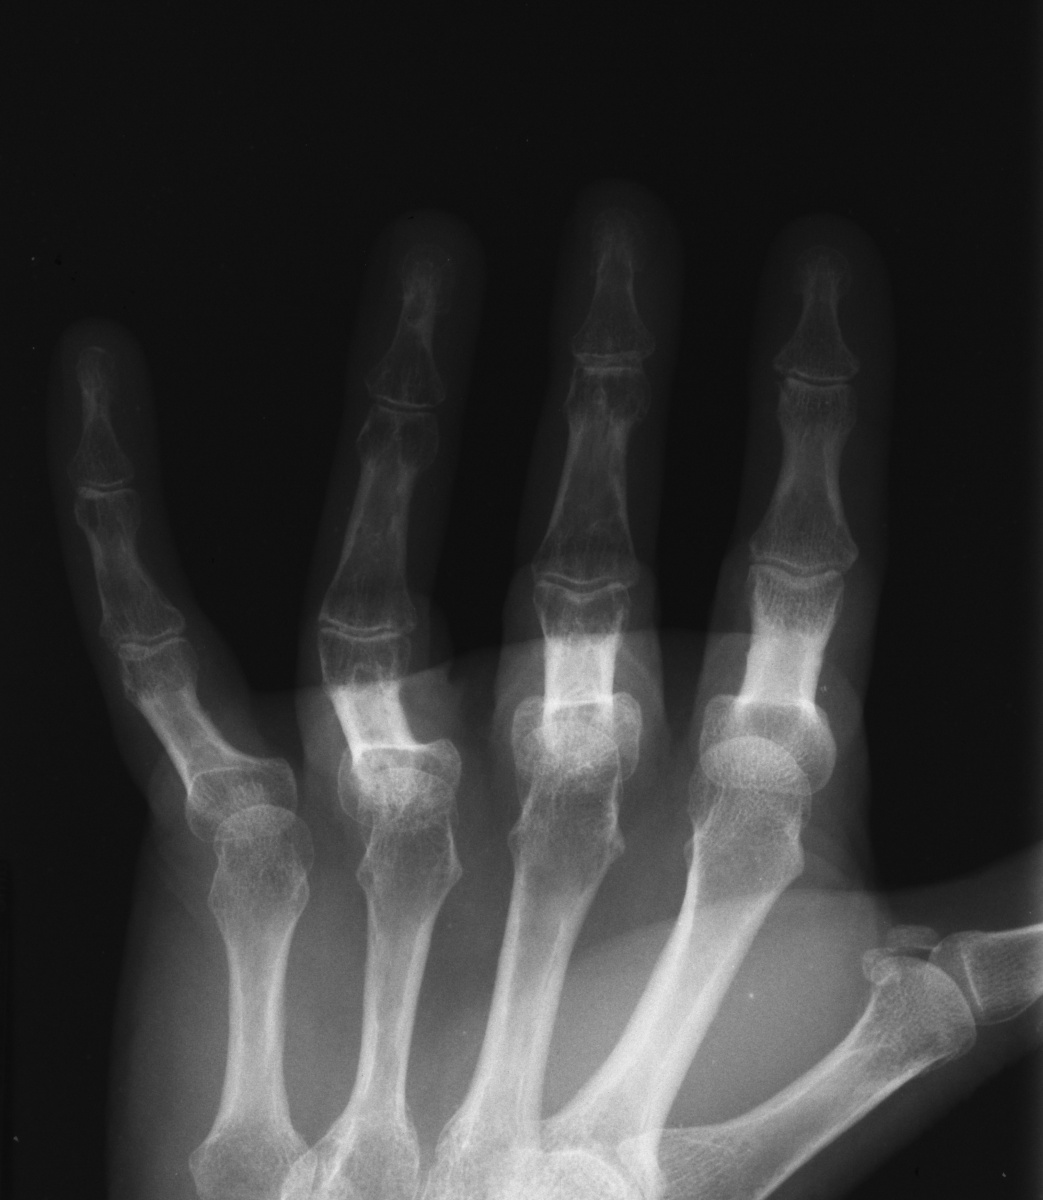

Modified AP views taken with the middle phalanges flat on the radiograph plate show preservation of joint anatomy.